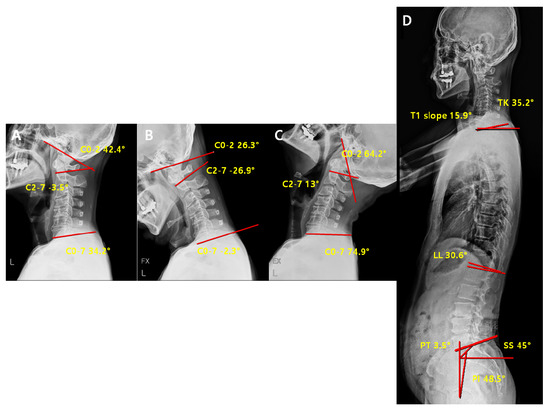

| Parameters | Definition |

|---|---|

| C2-7 Cobb angle | The intersection angle between the line perpendicular to the line parallel to the C2 lower endplate and the line perpendicular to the line parallel to the C7 lower endplate |

| C0-2 Cobb angle | The occipito-cervical angle, which is the intersection angle between the McGregor line and the line parallel to the C2 lower endplate and is used to evaluate the curvature of the upper cervical spine |

| C0-7 Cobb angle | The intersection angle between the McGregor line and the line parallel to the C7 lower endplate |

| C0-2/C0-7 | The value of C0-2 Cobb angle divided by C0-7 Cobb angle |

| C2-7/C0-7 | The value of C2-7 Cobb angle divided by C0-7 Cobb angle |

| T1 slope | The intersection angle between the tangent line and the upper plate of the T1 vertebral body |

| SS (Sacral Slope) | The angle formed by a line drawn along the endplate of the sacrum and a horizontal reference line |

| PT (Pelvic Tilt) | The angle formed by a line drawn from the midpoint of the sacral endplate to the center of the bicoxofemoral axis and a vertical and a vertical plumb line |

| PI (Pelvic incidence) | The angle formed by two vectors: (1) The line joining the bicoxo-femoral axis to the center of the sacral end plate and (2) A line perpendicular to the sacral endplate |